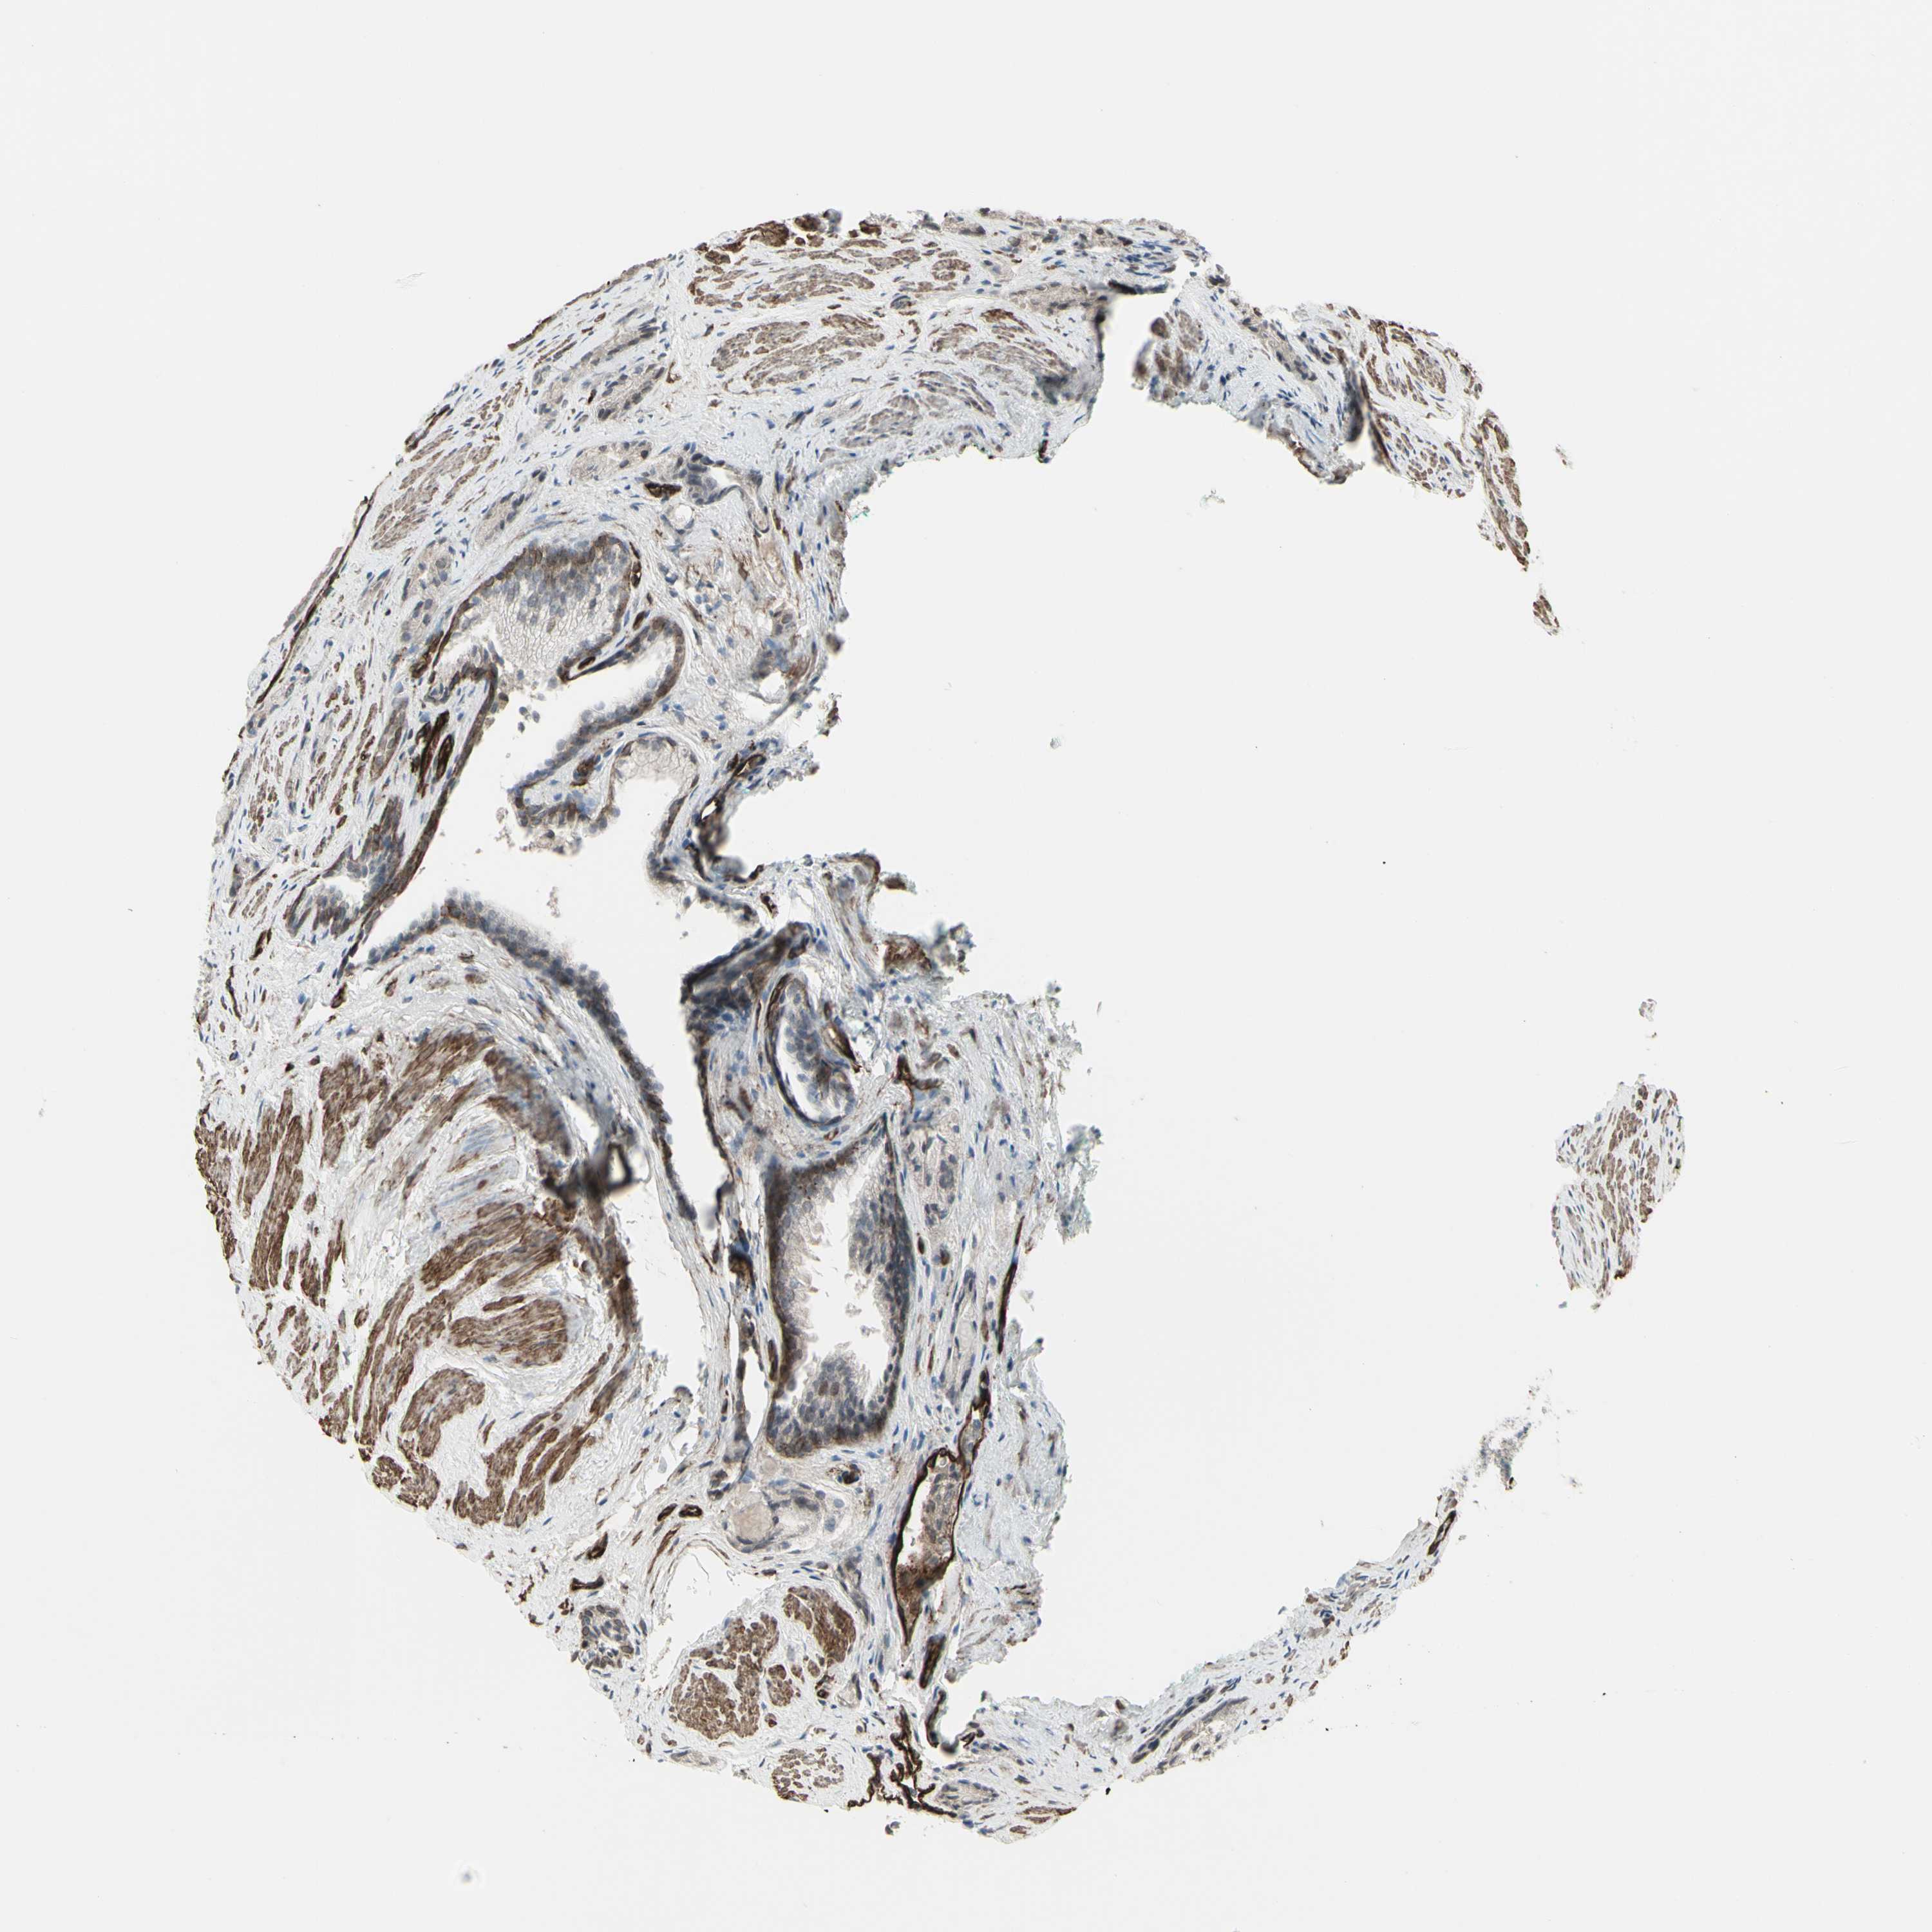

PROSTATE CANCER - Protein expressioni

A mouse-over function shows sample information and annotation data. Click on an image to view it in a full screen mode. Samples can be filtered based on level of antibody staining by selecting one or several of the following categories: high, medium, low and not detected. The assay and annotation is described here.

Note that samples used for immunohistochemistry by the Human Protein Atlas do not correspond to samples in the TCGA dataset.

Antibody stainingi

Antibody staining in the annotated cell types in the current human tissue is reported as not detected, low, medium, or high, based on conventional immunohistochemistry profiling in selected tissues. This score is based on the combination of the staining intensity and fraction of stained cells.

Each image is clickable and will lead to virtual microscopy that enables deeper exploration of all samples and also displays staining intensity scores, fraction scores and subcellular localization as well as patient and tissue information for each sample.

Antibody HPA010570

Staining

High

Medium

Low

Not detected

Intensity

Strong

Moderate

Weak

Negative

Quantity

>75%

75%-25%

<25%

None

Location

Nuclear

Cytoplasmic/membranous

Cytoplasmic/membranous,nuclear

Adenocarcinoma, Low grade

Adenocarcinoma, High grade